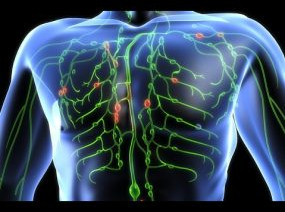

Kaj je limfa?

Limfna tekočina je naš naraven čistilec telesa in najpomembnejši del imunskega sistema. Odvaja toksine, viruse, bakterije, težke kovine in vso nečistočo iz telesa preko naravnih izločkov (urin, pot, blato…). Brani telo pred okužbami mikroorganizmov.

limfni sistem z bezgavkami

Limfne tekočine je 2x več kot krvi

Imamo več kot 600 bezgavk v telesu

Limfni sistem nima črpalke

Limfna tekočina je prepredena po telesu po limfnih žilicah, podobno kot kri po krvnih. Preko majhnih limfnih kapilaric se strupi precejajo v večje in iz večjih v bezgavke, kjer jih nato telo skozi izločke vrže ven.

Majhne kot grahova zrna, ali večje celo od oreha filtrirajo toksine/mikroorganizme/strupe. Ko so preobremenjene otečejo. Povečane in otečene so večkrat lahko znak, da se telo bojuje z vnetjem. So pomemben del imunskega sistema. Največje so v dimljah, pod pazduhami, na vratu, prsih in v trebuhu.

Strupi se odvajajo iz telesa tako hitro, kakor hitra je limfna tekočina. Limfni sistem je za razliko od krvnega, ki ga poganja srce, odvisen od drugih mehanizmov. Poganja ga gibanje sklepnega mišičja, pulzacija arterij, dihanje in peristaltika, razlike o pritisku notranjih organov, pa tudi ročna limfna drenaža ter povijanje okončin. Za nemoten limfni pretok morajo ti mehanizmi delovati nemoteno, sploh dobro je redno gibanje in zadosti popite tekočine dnevno. Med najbolj učinkovite zunanje mehanizme uvrščamo ročno limfno drenažo.